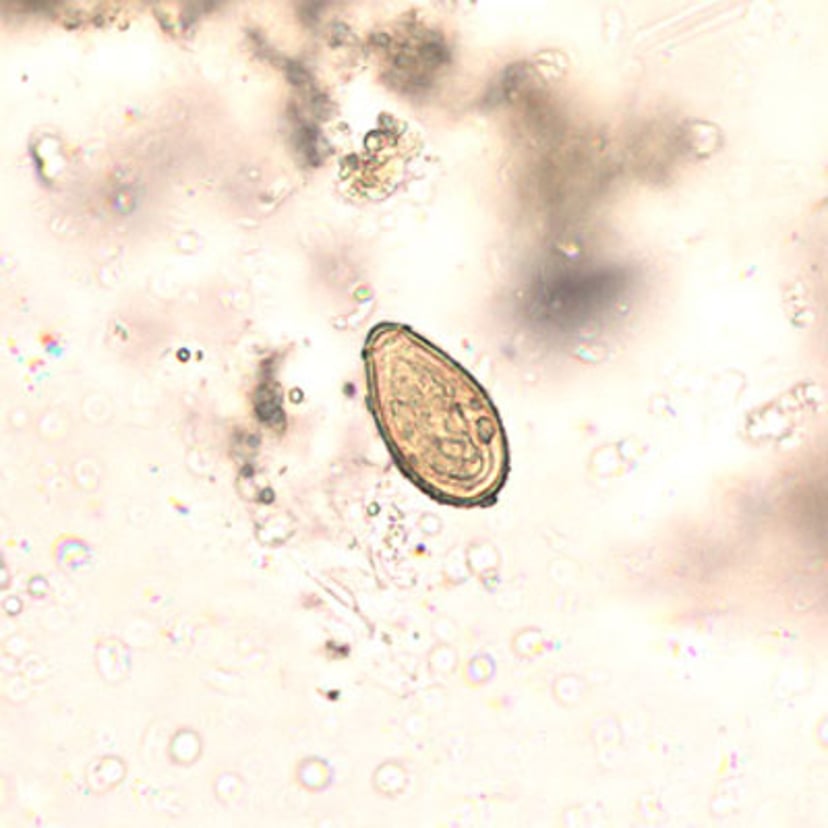

Opisthorchis Egg

Eggs of Opisthorchis species are 19 to 30 micrometers long by 10 to 20 micrometers wide. They are often indistinguishable from Clonorchis sinensis eggs. Opisthorchis eggs are operculated and have prominent opercular "shoulders" and an abopercular knob. The eggs are embryonated when passed in feces.